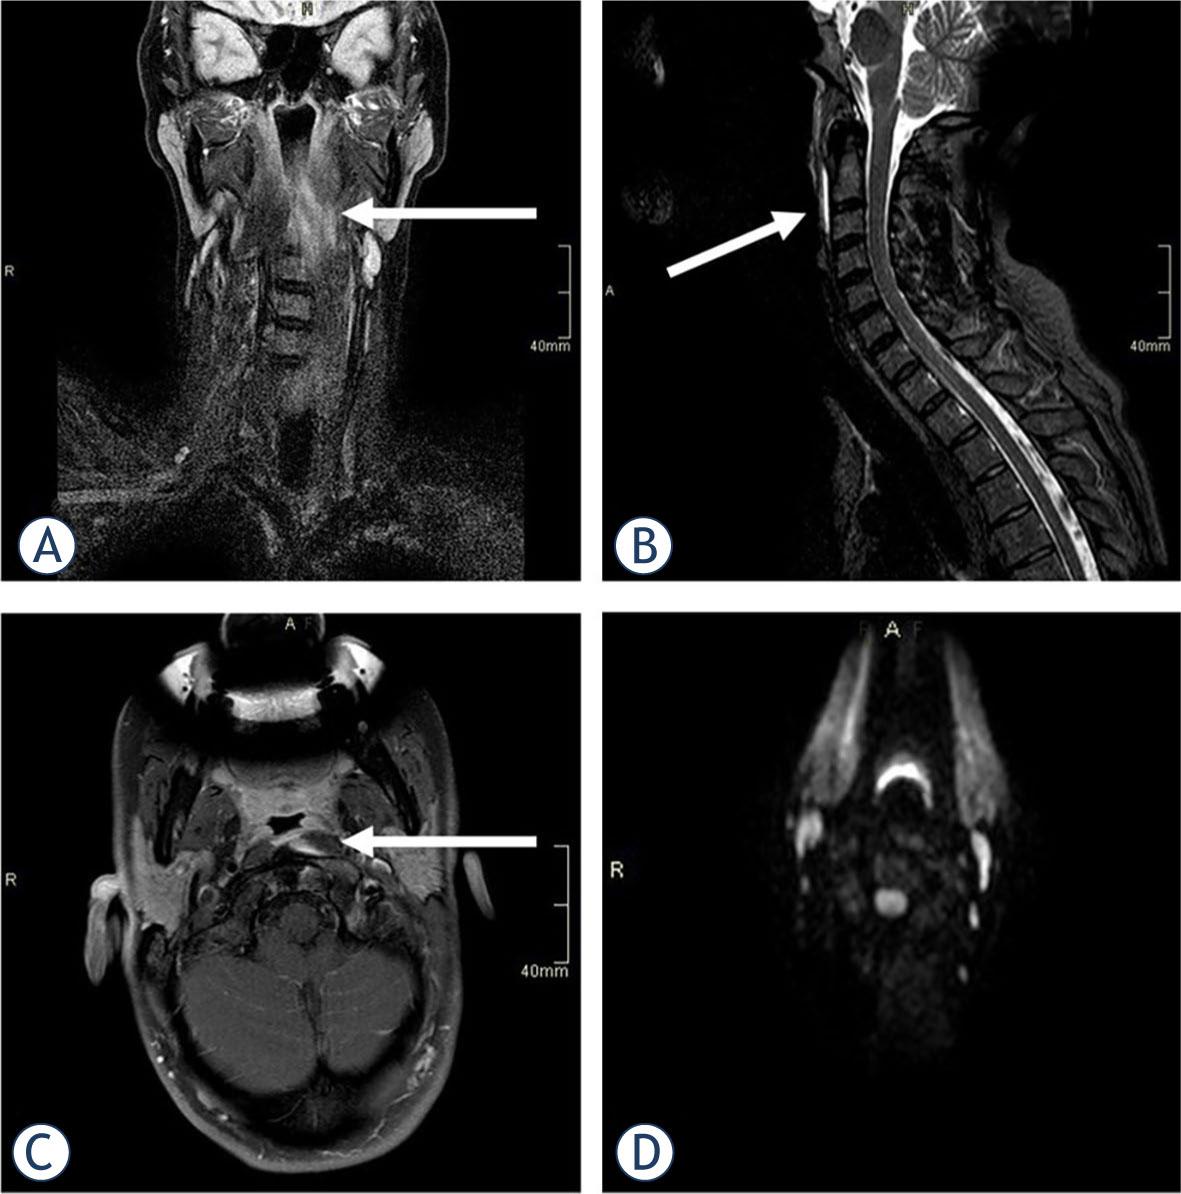

A previously healthy 40-year-old female with suspected meningitis was referred to our institution in November 2020. She was experiencing excruciating throbbing neck pain, which had developed spontaneously within 12 hours without any trauma or heavy mechanical load. She complained that swallowing was painful and that the pain increased with any attempt to move the head. A neurological exam showed severe neck stiffness with immobility in all directions as well as dysesthesia over the vertex and occipital regions. Laboratory workup revealed only mildly increased C reactive protein (CRP) of 20 mg/l (normal value < 5 mg/l) and white blood cell count (WBC) of 10.2 (normal < 10×109/l). Although the patient was afebrile, the retropharyngeal abscess was still considered in the differential diagnosis. Magnetic resonance imaging (MRI) of the neck showed fluid collection and swelling in the cranial part of the longus capitis/colli muscle on the left (Figure 1). A lumbar puncture was also performed, but the CSF was normal. She was treated in the NEU and discharged with ketoprofen 200 mg daily and a soft neck collar. The pain resolved in one month.

MRI in a 40-year-old female showed short tau inversion recovery sequence (STIR) hyperintensity in the upper part of her left Longus colli muscle, suggesting an oedema (A), with thin prevertebral effusion on sagittal images (B). After intravenous gadolinium contrast injection, a small area of enhancement was observed in the medial aspect of the muscle (C), but no peripherally enhancing collection to suggest an abscess was present. Diffusion-weighted imaging was normal, excluding the presence of pus (D).